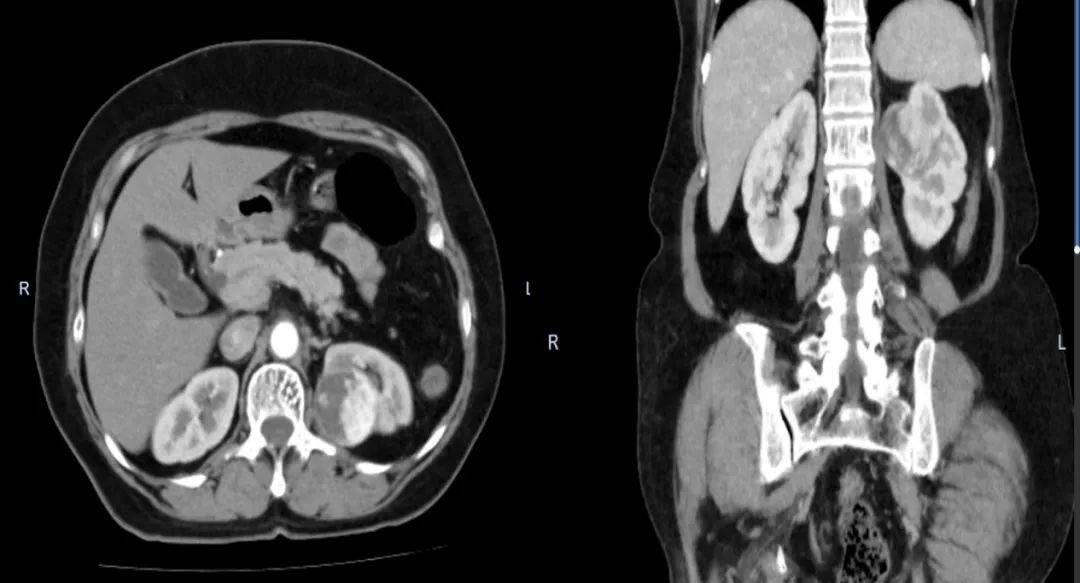

患者为中年女性,常规体检时发现左肾占位性病变。为进一步治疗,患者来到和田县人民医院王方明门诊,入院后完善腹部增强CT检查提示左肾恶性占位性病变,病灶直径6cm,若不及时治疗,患者将面临生命危险。

患者术前增强CT影像学检查结果(左为横断面,右为冠状位)

王方明认真分析患者病史以及影像学资料,主持病例分析和术前总结会,并与放射科共同研判CT结果。结合肿瘤性质和分期、患侧肾血管分布情况、局部淋巴结受累情况、健侧肾的功能等,经讨论,为减少患者创伤,助力术后快速恢复,王方明团队为患者制定了后腹腔镜下左肾肿瘤切除术。